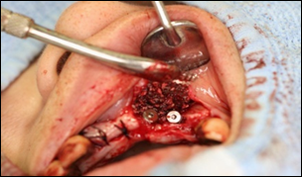

骨造成法

インプラントを埋めるための顎の骨の量が足りない場合に行う手術です。骨造成法には下記の種類があります。

GBR法

1:インプラントを入れた状態です。

骨が足りないためインプラント体が全て埋まらずに見えてしまっています。

2.1を上から見た図です

3.造骨に使用する補填剤です。

β-TCPという骨補填剤とPRPという血液から血小板を凝縮して作ったものと 自家骨を混ぜたものです。

4.チタンの膜を置いて歯ぐきと骨の間にスペースを作り、3の補填剤を入れます。

5.チタンの膜を骨の上に被せたところです。

真上からみた図

6.頬側から見た図

7.4ヶ月後にチタンの膜を取り除いたところです。

骨が新しく作られ、インプラント部が完全に埋まっていることがわかります。